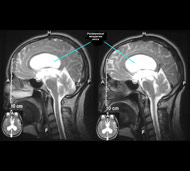

В МЦНХ освоили новый революционный метод оперирования водянки - нейроэндоскопический. Он широко применяется на Западе, но на постсоветском пространстве применяется редко из-за дороговизны оборудования и недостаточного опыта врачей.

Метод малотравматический и надежный. В отличие от шунтирования, которое длится час-два, операция занимает всего 10-20 минут. В каналы мозга заходят специальным устройством - нейроэндоскопом, содержащим мини-камеру. Изображение передается на экран и врачи видят, куда надо вести инструменты, чтобы восстановить отток жидкости. Суть операции заключается в создании оттока через дно третьего желудочка во внемозговые цистерны ликворной системы. Новообразованное отверстие создают специальным катетером. В результате - ликвор беспрепятственно вытекает из мозга, человек спасен навсегда. Больше не надо повторных операций или замены деталей.